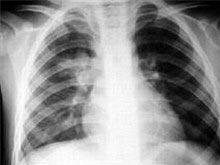

单纯性肺嗜酸粒细胞增多症(simple pulmonary eosinophilia)是由Loffler1932年首先报道的,故又称吕弗勒综合征(Lofflers syndrome)。特点为全身症状轻微,X线呈一过性肺部阴影,血嗜酸粒细胞增多,病程2~4周,亦称为急性肺嗜酸粒细胞增多症(acute pulmonary eosinophilia),患者可有个人或家族过敏史。